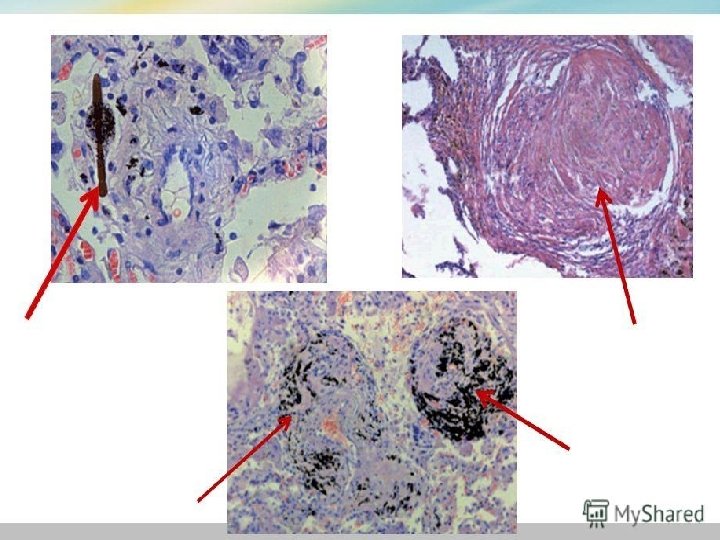

Диагноз: ПК. Распространенное усиление легочного рисунка за счет интерстициального компонента в виде сетчатости и мелкой ячеистости, на фоне которого во всех отделах легких видны очаговые тени до 0, 2 0, 4 см в диаметре

Диагноз: ПК. Распространенное усиление легочного рисунка за счет интерстициального компонента в виде сетчатости и мелкой ячеистости, на фоне которого во всех отделах легких видны очаговые тени до 0, 2 0, 4 см в диаметре

![. Диагноз: силикоз. Множественные затенения до 0, 1 0, 2] . Диагноз: силикоз. Множественные затенения до 0, 1 0, 2]](https://present5.com/presentation/e44541d1711586d4ba0c9c946d856ad1/image-13.jpg) . Диагноз: силикоз. Множественные затенения до 0, 1 0, 2]

. Диагноз: силикоз. Множественные затенения до 0, 1 0, 2]